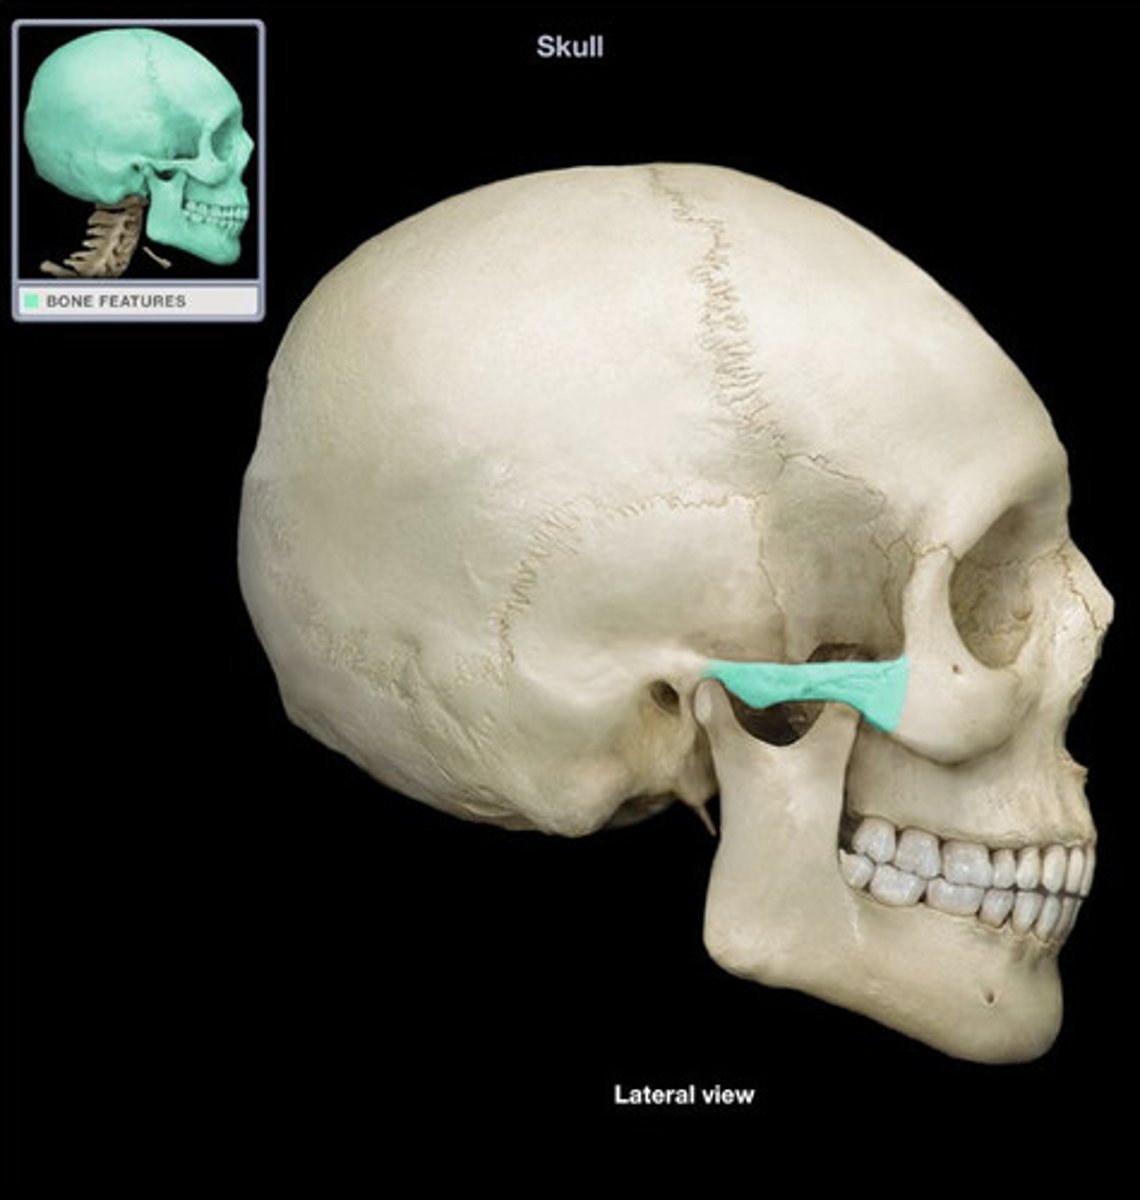

- zygomatic arch

- formed by the union of temporal process of zygoma and zygomatic process of the temporal bone

What is this and how is it formed?